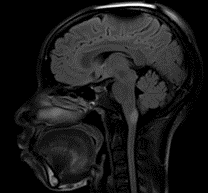

Debido a la evolución tórpida de la paciente, su familia fue interrogada sobre el estado de la paciente, a lo que el familiar agregó síntomas adicionales consistentes en episodios de accesos de tos con posterior alteración de la conciencia y movimientos anormales en las extremidades compatibles con crisis epiléptica tónica clónica bilateral con amnesia del evento. Se sospechó una etiología en el sistema nervioso central por lo que, posteriormente, se solicitó una resonancia magnética contrastada del cerebro; esta reportó una lesión única hiperintensa en la secuencia T2 en el área postrema; por lo tanto, se enfocó como un posible SAP (Imagen 1). Para descartar posibles etiologías se realizó una punción lumbar que informó presión de apertura de 26 cmH2O, 1 linfocito, glucosa 56mg/dL, proteínas 26 mg/dL; Gram/Tinta china/Panel molecular para meningitis fueron negativos. Además, los cultivos para bacterias, hongos, micobacterias, PCR-RT para tuberculosis y bandas oligoclonales fueron todos negativos. Dado lo anterior, se decidió cambiar el esteroide de prednisolona a hidrocortisona 100 mg cada 8 horas. La paciente mejoró significativamente después de este ajuste hasta el punto en que sus síntomas cesaron, y pudo ser dada de alta con una fórmula médica.

Imagen 1. A) RM del cerebro en corte sagital, en secuencia T1, donde no se observa hallazgo patológico evidente. B y C) RM del cerebro en plano axial en secuencias T2 y FLAIR, donde una lesión hiperintensa concéntrica se observa en el área postrema.

Imagen 1. D y E) RM del cerebro en plano axial, en secuencia T1, TRACE y ADC donde no se observa restricción a la difusión. F) RM del cerebro en el plano axial, secuencia T1 post contraste donde no se observa realce de la lesión descrita.